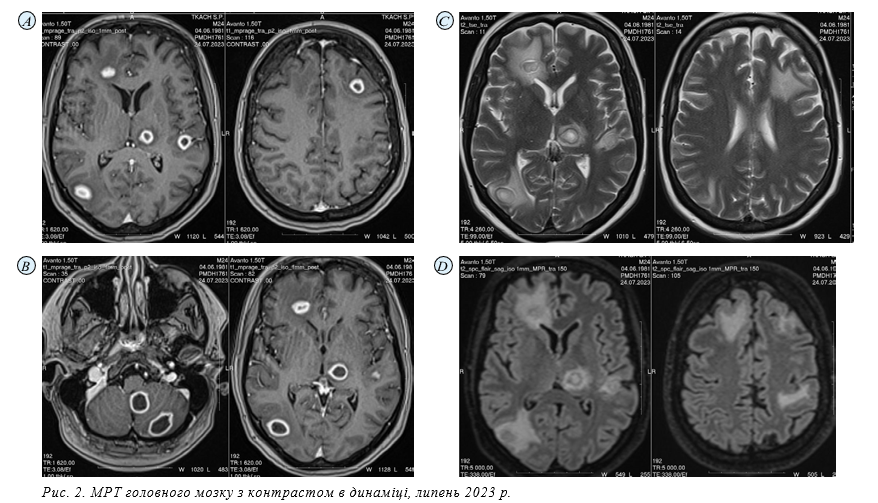

24.07.23 МРТ головного мозку з контрастом. Протокол сканування: виконані T2WI, T2_spc_flair_iso, T1WI, DWI, SWI

томограми головного мозку у аксіальній, корональній та сагітальній проєкціях, T1_mpr + C з подальшою мультипланарною реконструкцією.

МР-картина множинного вогнищевого ураження супра- та інфратенторіальних відділів головного мозку, що за МР-характеристиками може більш ймовірно відповідати множинним внутрішньомозковим абсцесам (бактеріальної/фунгальної/специфічної етіології?). Супутня знахідка: звертає на себе увагу наявність при попередній МРТ округлого вогнища в зоні верхньої щелепи праворуч (верхній зубний ряд праворуч) дотично до нижньої стінки правої верхньощелепної пазухи діаметром до 14 мм, з ознаками обмеження коефіцієнта дифузії (не виключно, одонтогенний абсцес/ інфільтрат?), який при поточному обстеженні має розміри ≈14х13х13,3мм, неоднорідно периферично накопичує контрастний препарат.

Враховуючи супутню знахідку — ймовірний абсцес/ інфільтрат в зоні верхньої щелепи праворуч, слід виключати одонтогенну природу внутрішньомозкового ураження. Порівняно з попередньою МРТ визначається деконфігурація вогнищ, зміна їх розмірів та зон перифокального набряку, потовщення периферичних зон накопичення контрастного препарату, що відповідає капсулам (ймовірно, відображає стадійність формування абсцесів). Кількість вогнищ попередня (13), появи нових вогнищ не визначається. Залишається актуальним виключення вторинного ураження (рис. 2 а, b, c).